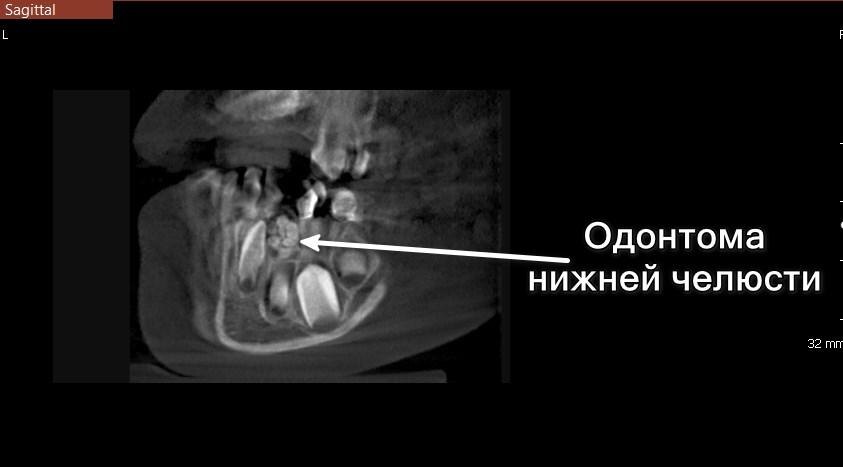

Одонтома в области зуба 8.2 — срез КТ

На повторном приеме в 4 года детский стоматолог обнаружил у Сережи большое количество кариесов. Перед объемным лечением направили мальчика на панорамный снимок, где выявили образование в переднем отделе нижней челюсти в области зуба 8.2.🧐

Для уточнения диагноза и планирования лечения провели компьютерную томографию и пригласили хирурга для консультации. По снимкам КТ образование больше всего напоминало одонтому, состоящую из фрагментов несформировавшихся зубов.

Одонтома — это доброкачественная опухоль (одонтогенная опухоль), возникающая из тканей, участвующих в формировании зубов: эмали, дентина, цемента и пульпы. Она чаще всего встречается у детей и подростков. Может быть обнаружена случайно на рентгеновском снимке, так как обычно протекает бессимптомно.